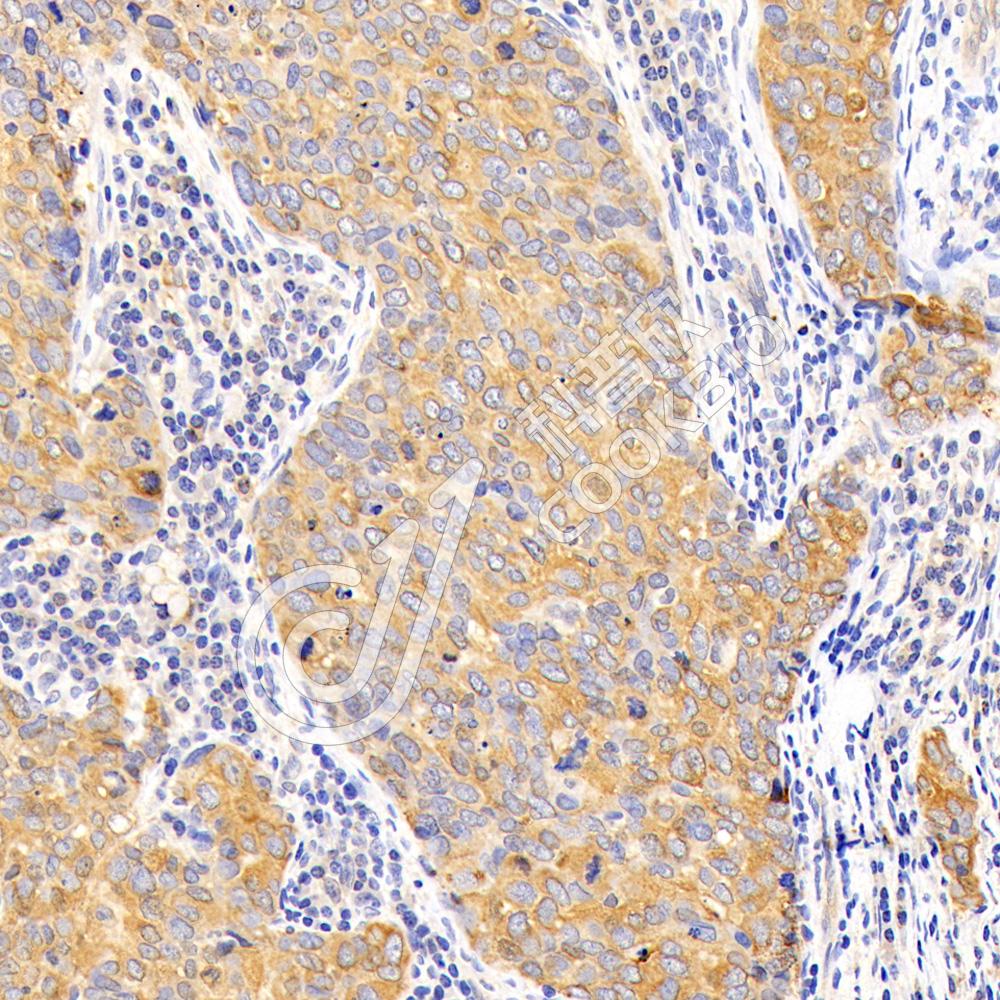

IHC检测SRGAP1蛋白(货号 K1340242).

样品: 人食管癌, 4%多聚甲醛 (货号KSG1101) 固定12-24小时.

抗原修复: 柠檬酸抗原修复液(干粉, pH 6.0) (KSG1201), 98℃, 20分钟.

—抗: 1: 500稀释, 4℃ 孵育过夜.

二抗: S-vision免疫组化多聚二抗(山羊抗兔),即用型 (货号KB3906), 室温孵育20分钟.

样品: 人肺癌, 4%多聚甲醛 (货号KSG1101) 固定12-24小时.